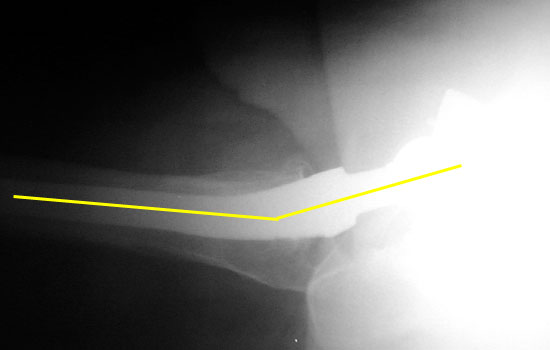

Femoral component should be anteverted. Exact degree of optimal anteversion is unknown

Femoral neck anteversion is difficult to accurately evaluate on radiographs, and can only be qualitatively assessed on a groin lateral view. This view is difficult to obtain, especially in the elderly or post operative patient, and is effected by pelvic or thigh rotation.

CT is the imaging modality of choice to evaluate for femoral neck anteversion.

Femoral neck anteversion on groin lateral film.

Version of acetabular and femoral components may be cumulative. Therefore, a retroverted cup can be compensated by an anteverted femoral component